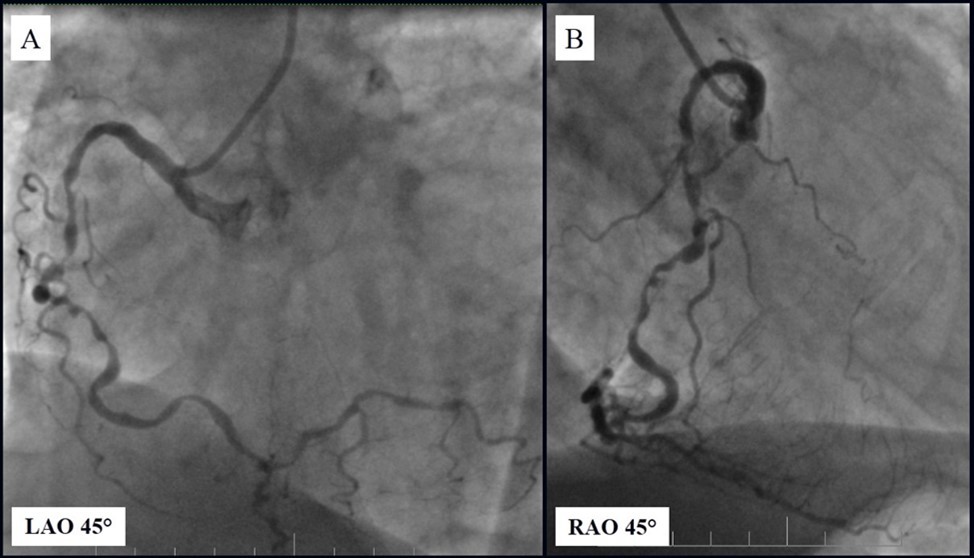

Angiography revealed rare anatomical variation LMCA quadrifurcation (Figure 1, Figure 2), 50% stenosis of the distal part of the LMCA, 40% stenosis of the ostial segment of left anterior descending (LAD) artery and diffuse prolonged 70-75-95% stenosis in mid-segment (Figure 3), 75% stenosis of the ostial segment of the circumflex (CX) artery, 75% stenosis of the ostial segment of the first marginal branch (OM1), 75-90% stenosis of the proximal segment of the intermediate artery (IMA), prolonged diffuse severe 90-95% stenosis of mid-segment of the right coronary artery (RCA) (Figure 4).

Figure 3.Prolonged diffuse severe 90-95% stenosis of mid-segment of the right coronary artery. A - Left anterior oblique 45° projection; B – Right anterior oblique 45° projection.